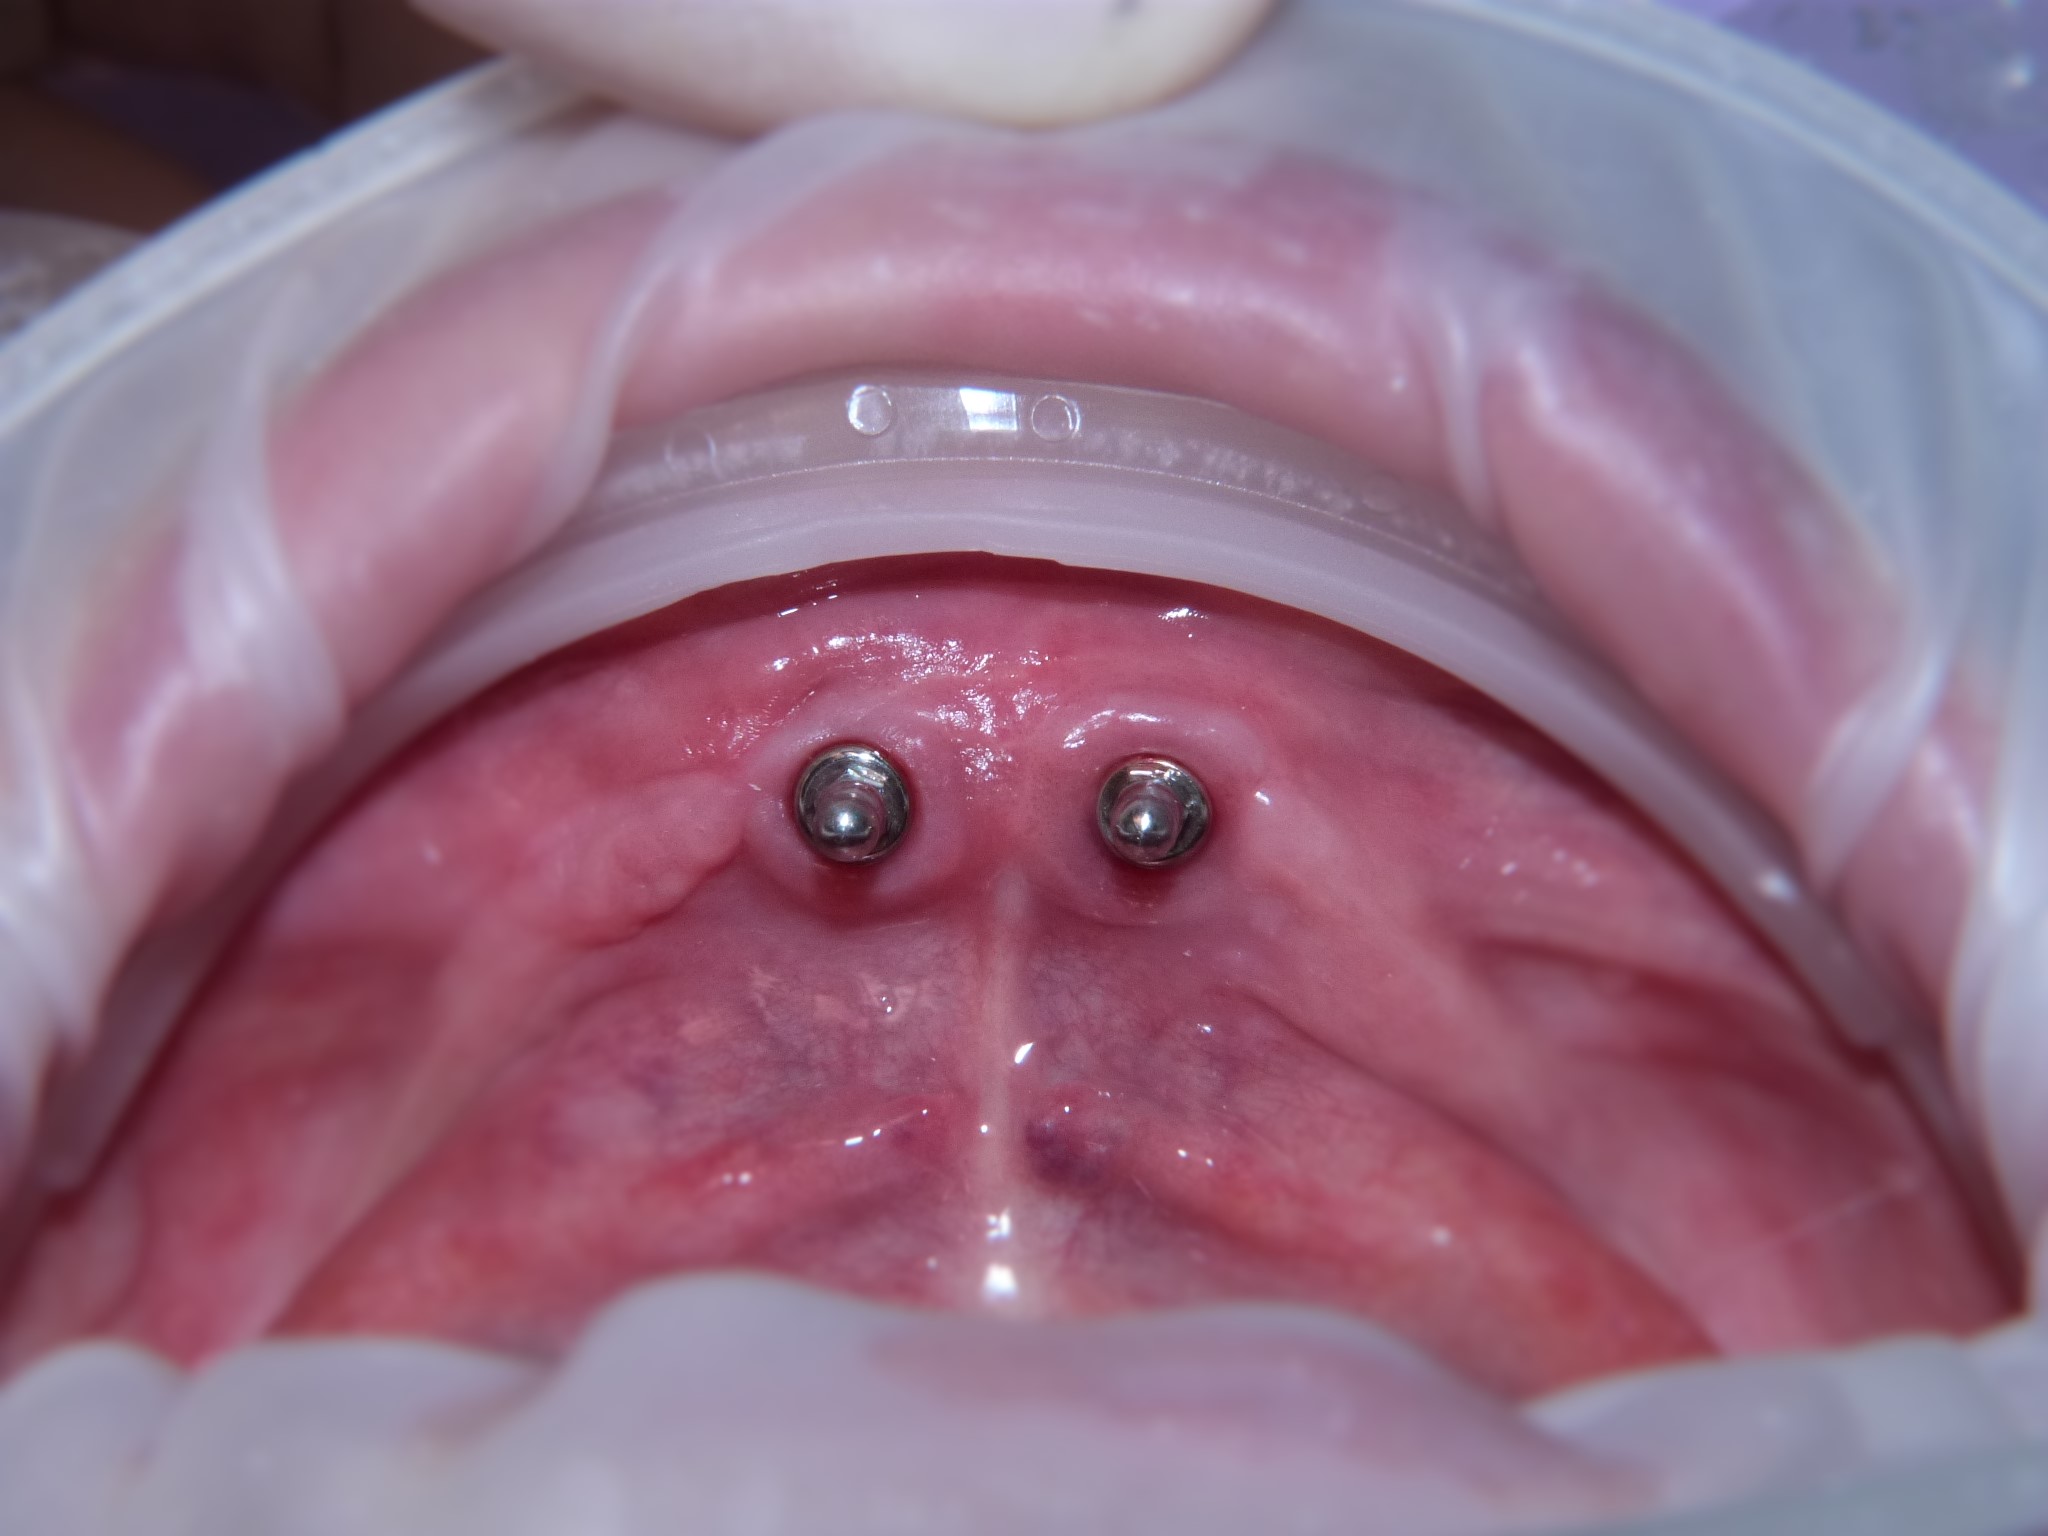

I dispositivi di ancoraggio utilizzati per le overdentures sono diversi (attacchi sferici, barre rotazionali, barre con patrici, Locator® ecc.) cosicché cambiano anche le strutture di ritenzione interne alla protesi.

Nel presente caso clinico viene illustrata la riabilitazione protesica di una paziente parzialmente edentula che per l’ irrecuperabilità dell’unico elemento dentario residuo intende sostituire la sua protesi mobile inferiore con una protesi mobile completa di tipo overdenture. Si decide così di inserire due impianti nella regione incisale inferiore mantanendo l’elemento da estrarre e la protesi preesistente durante il periodo di osteointegrazione degli impianti. A tre mesi si bonifica l’ elemento dentario gravemente parodontopatico e si completa la protesizzazione con la realizzazione di una protesi mobile completa di tipo overdenture con ritenzioni per attacchi sferici.